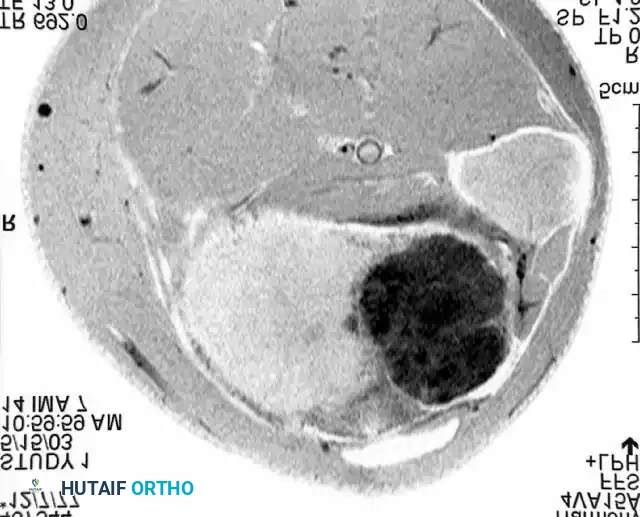

Advanced imaging, such as the MRI cross-section above, is mandatory for preoperative planning to delineate the tumor's relationship to neurovascular structures and compartmental boundaries.

Understanding compartmental anatomy, as illustrated in this cross-section of the thigh, is paramount when planning wide or radical resections.